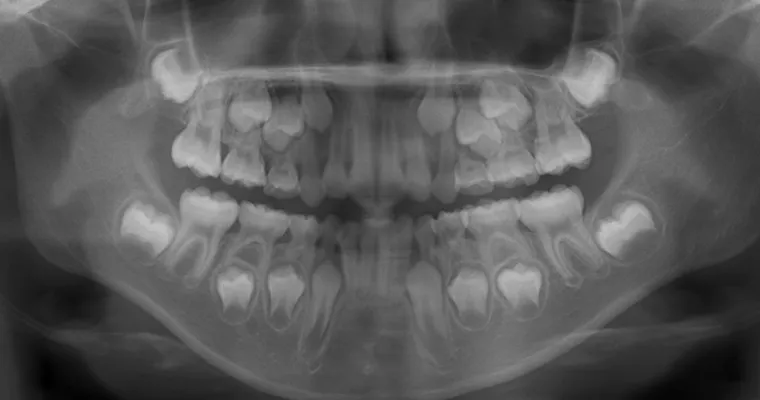

治療前 パノラマレントゲン